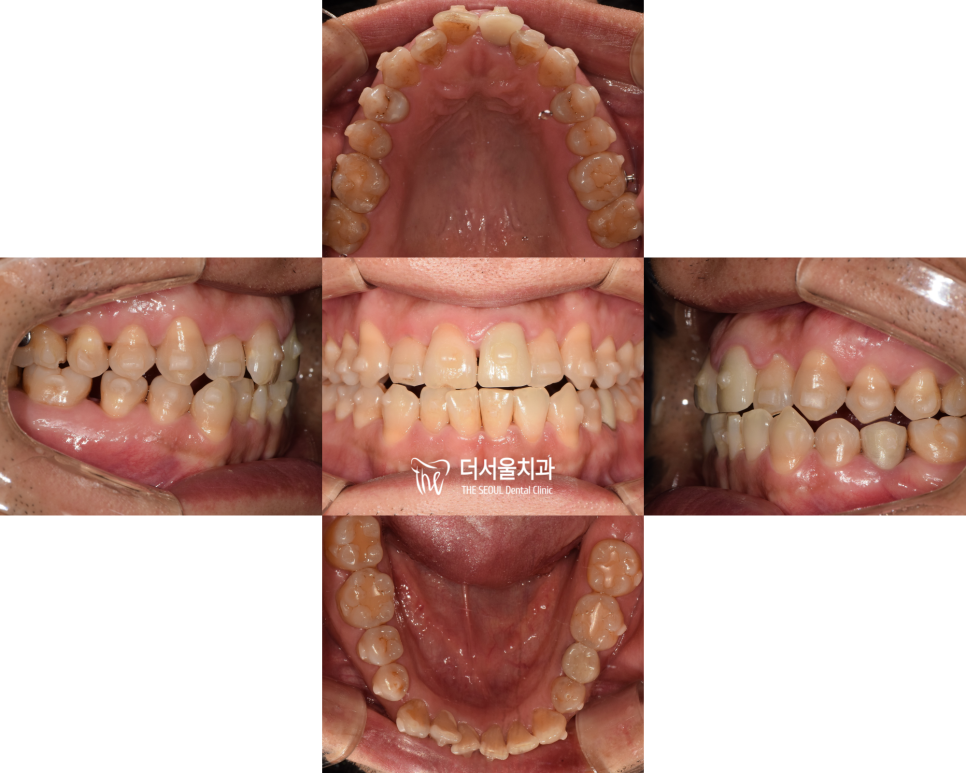

【 진행 과정 】

치아들을 이동시키려면,

공간을 확보해야 되기 때문에

일단, 상악(윗 턱)은 어금니(구치부)쪽은 그대로

둔 채 앞니쪽만 앞으로 이동시키기로 했습니다.

그리고, 하악(아래턱)은 어금니쪽들을 뒤쪽으로

먼저 밀어놓고, 공간을 확보 한 다음 전치부를

뒤쪽으로 밀어내기로 계획을 했습니다.

이에 맞게 단계를 쪼개어 장치를 만들었습니다.

순조롭게 이동을 하고 있는 모습인데요.

어태치먼트와 버튼을 사용하여

좀 더 긴밀한 배열을 유도했습니다.

또한 반대교합이 나타난 곳도

신속히 개선을 도왔는데요.

이곳을 고치지 않으면

추후 치아 파절의 원인이 될 수 있기 때문이죠.